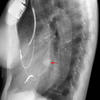

PA angio

Fig 4